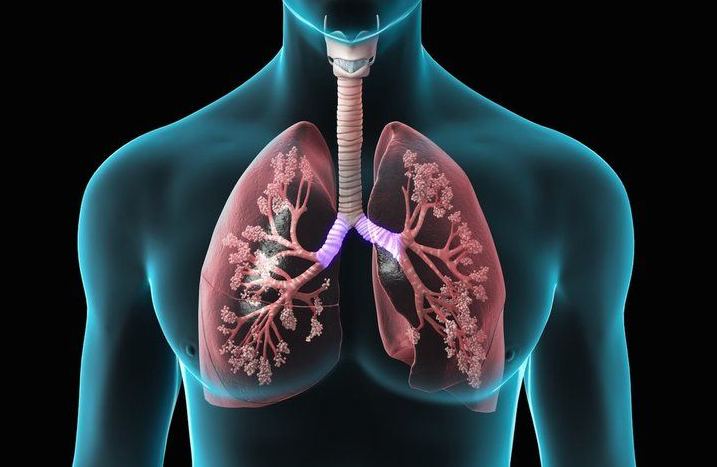

أجرى فريق طبي مصري متخصص ومدرب في جامعة عين شمس التخصصي، وبالمشاركة مع فريق ياباني متخصص ومتمرس في زراعة الرئة عن طريق الأحياء، أول عملية لزراعة الرئة في مصر، بعد شهور عديدة من التحضير، لتدخل البلاد مرحلة جديدة في مجال زراعات الأعضاء.

فزراعة الرئة تُساهم في إنقاذ حياة آلاف المرضى المصريين الذين يعانون من أزمات حادة في الجهاز التنفسي، وباتت هذه الجراحات والزراعة ملاذهم الوحيد.

وفي تصريح ، أوضح الاستاذ الدكتور طارق محسن رئيس وحدة جراحة الصدر في طب القصر العيني، أنه يوم الأربعاء الماضي تم عملية زراعة الرئة لأول مرة في مصر، في مستشفيات عين شمس التخصصي، وكان المتبرع أخو الحالة بحسب تصريح جامعه عين شمس

وأضاف، أنه بشكل عام يستغرق هذا النوع من العمليات أي عملية زراعة الرئة من 8 إلي 10 ساعات، ولا يتم إقرار نجاح العملية إلا بعد مرور عده ايام من الزراعة، ولا يخرج المريض من المستشفي قبل مرور عدة أسابيع حتي الإطمئنان علي حالته الصحية.

أشار رئيس وحدة جراحة الصدر، أن التحضير لعملية زراعة الرئة التي تمت في مستشفيات عين شمس كان أكثر من عده أشهر بخلاف تدريب استمر عده سنوات، مشيرا إلي أن التحضير يأخذ وقت طويل لأنه يعد أساس نجاح عملية الزراعة.

وأضاف رئيس وحدة جراحة الصدر، أن التحضير للعملية يتم عن طريق تقيم حالة المريض والمتبرع، ويشمل حالتهم الصحية من الناحية الطبية، وحالتهم العامة، فبالنسبة للمتبرع يجب أن يكون حالته الصحية جيدة، ولا يعاني من أمراض مزمنة ولا مدخن ولا يعاني من أمراض معدية كالتهاب الكبد الوبائي.

أما المريض، فيكون خضوعه لزراعة الرئة هو أخر أمل له في الشفاء من فشل التنفس الذي يعاني منه، أي عندما يكون خضع لجميع طرق العلاج الدوائية والجراحية ولا يستجيب، ولن يتعافي من المرض المسبب للفشل الرئوي إلا بالزراعة.

وأضاف طارق محسن، أن اختيار المريض والمتبرع يأخذ الكثير من الاستعدادت الطبية الدقيقة، ويضع كلايهما لإجراء تحاليل الصفات الوراثية ، ففترة التحضير مهمة لأنها يترتب عليها نجاح عملية الزراعة.

أوضح رئيس وحدة جراحة الصدر، أن ما بعد العملية يحتاج المريض للعديد من العلاجات أهمها أدوية مثبطات المناعة لتجنب رفض الجسم العضو الجديد، ويحتاج المريض لمتابعة دورية لتجنب التعرض لمضاعفات المترتبه عن استخدام ادويه المناعة، وهذا يجعله أكثر عرضة للعديد من الأمراض كالفيروسية أو اورام الغدد الليمفاويه .

ولذا المتابعة بعد الخضوع لعملية زراعة الرئة تعد من أهم السبل التي تحمي المرض من تعرضه لرفض العضو، الجديد و المضاعفات المترتبه عن مثبطات المناعه.